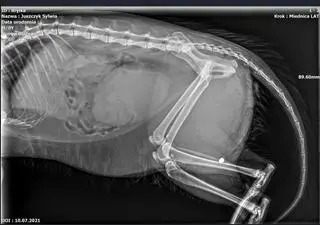

- Przyszłam z obiadu, a Bryłka na korytarzu czołgał się na brzuszku. Krew miał na grzbiecie, myśleliśmy że samochód go potrącił - opowiada pani Teresa, pensjonariuszka Domu Pomocy Społecznej. Rentgen wykrył trzy postrzały. Śrut utkwił przy kręgosłupie i nie można go wyciągnąć. Policja szuka strzelca.

Wizyta u lekarza weterynarii i zdjęcia rentgenowskie wykazały jednak, że kot ma w ciele trzy śruciny. Pani Teresa: - Dwa w łapce, jeden blisko kręgosłupa.

DPS zaalarmował Fundację Pet Patrol. - W tylnych łapkach był paraliż. Po wdrożeniu leczenia kot stanął na nogi, ale śrut w kręgosłupie poraził układ nerwowy - mówi Izabela Kozieł, prezeska Pet Patrol. Usunięcie jest ryzykowne dla życia kota, więc lekarze się na razie wstrzymują. Bryłka zaczął się samodzielnie załatwiać, ale ciągle ma problem z zapaleniem pęcherza.